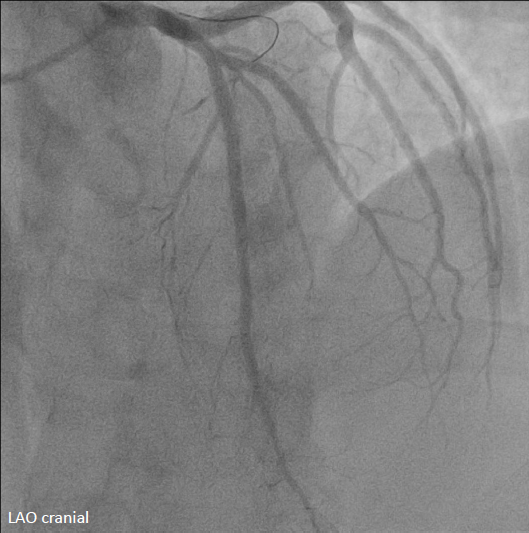

Emergent cardiac catheterization revealed patent left main coronary artery with total occlusion of the proximal left anterior descending artery (LAD). The left circumflex and right coronary arteries were patent. The culprit lesion was the proximal LAD.

The left coronary artery was engaged with an XB 3.5¡¿6 Fr guide catheter. Using a Fielder FC guidewire with a Fine-Cross microcatheter, the distal LAD was successfully accessed. Pre-dilation with a 1.5¡¿20 mm balloon demonstrated residual stenosis with poor flow. Further dilation with a 2.0¡¿15 mm balloon improved flow. Intravascular ultrasound (IVUS) revealed intramural hematoma (IMH) in the proximal-to-mid LAD. A drug-eluting stent (BMX6 2.75¡¿33 mm) was deployed from the proximal LAD (distal to the first diagonal branch) to the mid LAD, followed by proximal post-stent dilation with a 4.0¡¿12 mm non-compliant balloon at 4-16 atmospheres. Post-deployment IVUS confirmed adequate stent expansion without malapposition. Final coronary angiography demonstrated TIMI grade 3 flow.